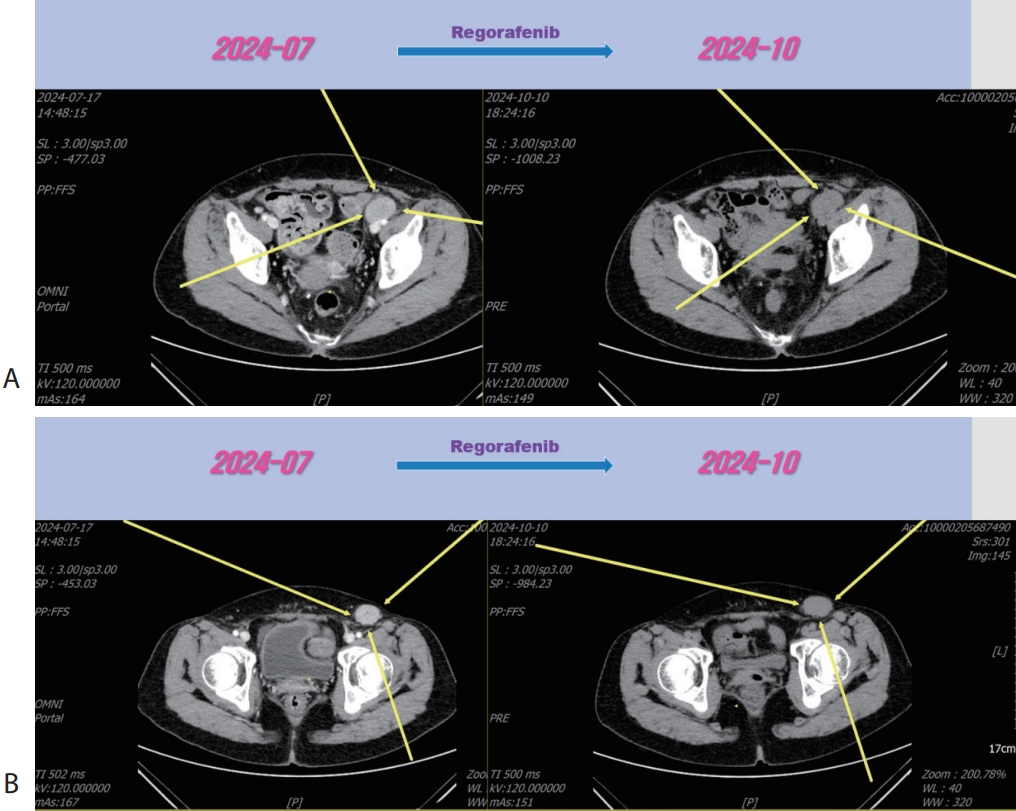

Fig. 4). Then the patient was treated with 3rd line regorafenib (Stivarga

®, 40 mg per dose; Bayer) for 3 months and LN metastasis was slightly increased (

Fig. 5), then we decided to combine RT for LN metastasis (40 Gray/16 fraction). Then the LN metastasis was markedly decreased (

Fig. 6). We are keeping on treating the patient with regorafenib therapy for over 12 months. We summarized treatment timeline of patient (

Figure 5.Liver CT scan (A, B) after 3rd line regorafenib therapy. Pelvic (A) and inguinal (B) lymph node metastasis were slightly increased after regorafenib therapy. CT, computed tomography.

Figure 6.Liver CT scan (A, B) after combination therapy of RT and 3rd line regorafenib. Slightly increasing pelvic (A) and inguinal (B) lymph node metastasis were marked shrinked after combination therapy. CT, computed tomography.